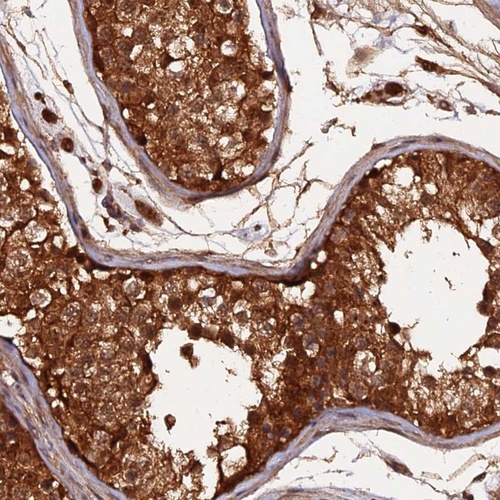

Immunohistochemical staining of human testis shows nuclear and cytoplasmic positivity in cells in seminiferous ducts.